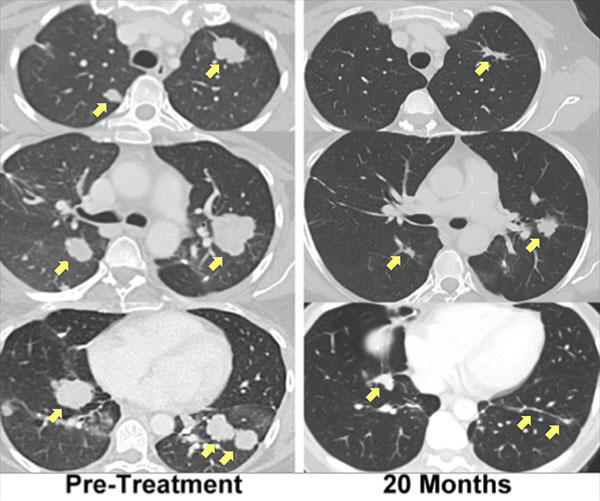

Side-by-side comparison of lung CT scans highlighting changes over time. The left column shows "Pre-Treatment" images with visible tumors indicated by yellow arrows. The right column shows scans "20 Months" post-treatment, with significant reduction in tumor size, as pointed out by the arrows.

A patient with metastatic bile duct cancer, treated with immunotherapy using her own mutation-specific T cells, has experienced regression of her metastatic lung and liver tumors that is ongoing for more than 2 years.

Credit: National Cancer Institute / Steve Rosenberg, M.D.

Last year his research team reported that T cells directed against a unique mutation in the tumor of a woman with advanced cholangiocarcinoma (bile duct cancer) were identified in lung metastases. The patient then underwent adoptive cell transfer, using an expanded pool of her own mutation-specific T cells, and experienced regression of her metastatic lung and liver tumors that is ongoing for more than 2 years.